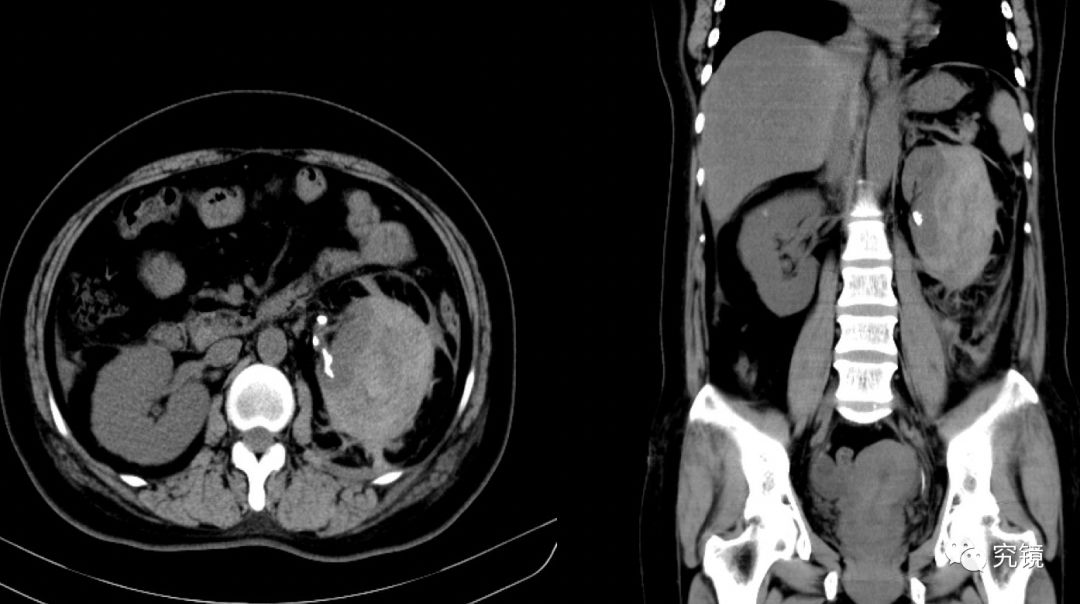

腹部实质性脏器外伤的ct表现_血肿